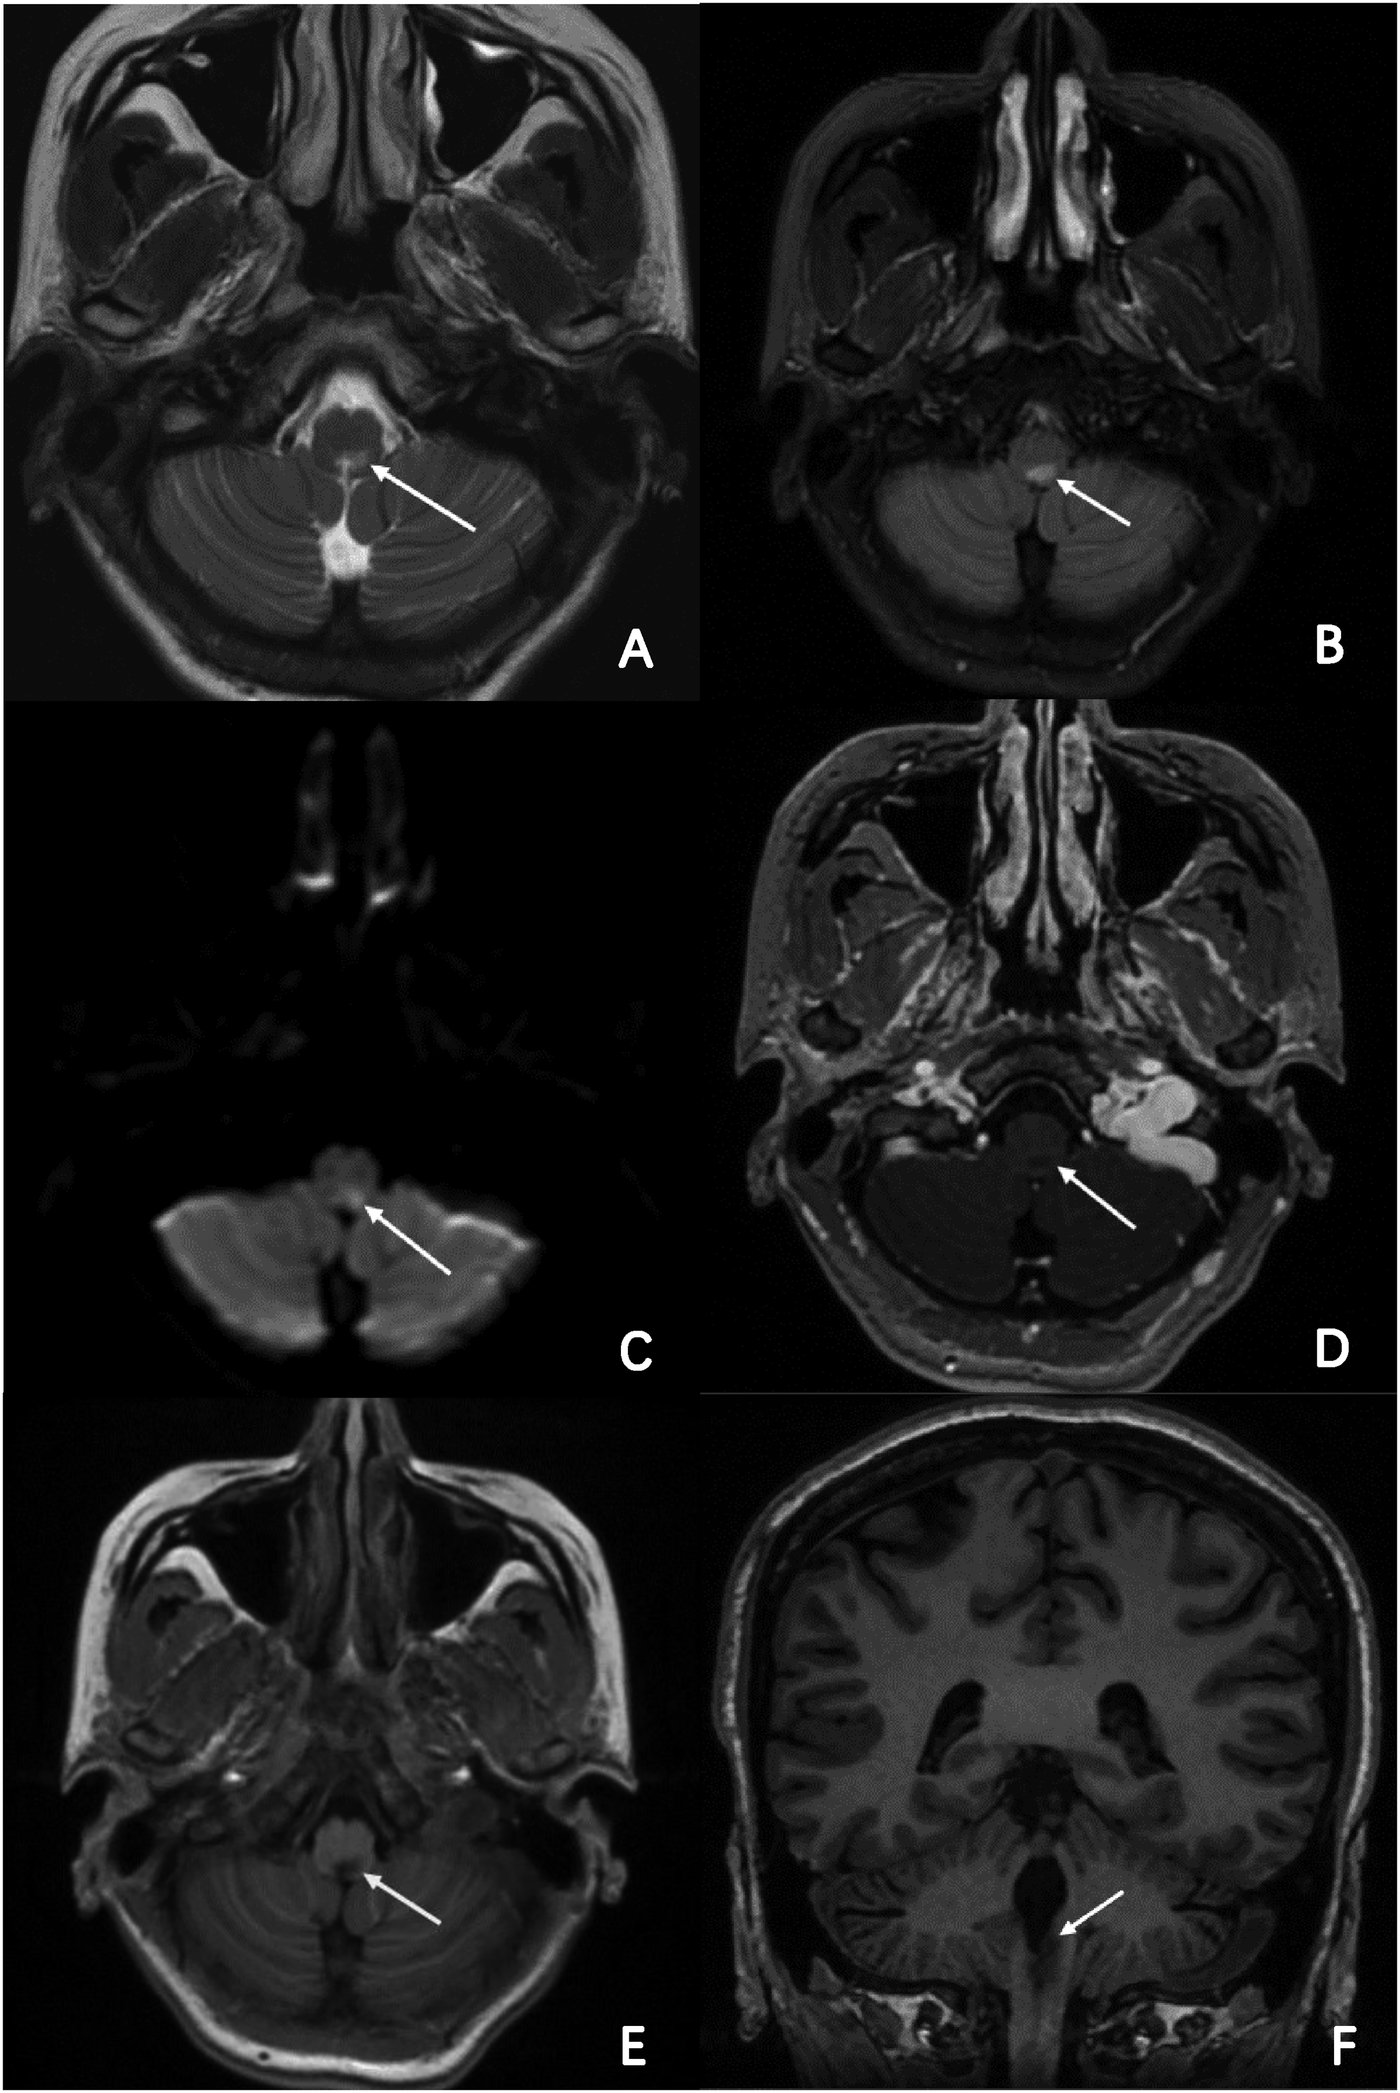

Figure 3

MR imaging of the brain and part of cervical cord. Axial T2-weighted, FLAIR and DWI brain MRI revealed a high-intensity lesion in the dorsal part of the medulla oblongata and cervical cord. (A–C; arrowheads) Axial enhanced T1-weighted and normal T1-weighted brain MRI revealed a low-intensity lesion in the same segment, (D,E; arrowheads) and clearer in coronal view. (F; arrowheads).

The patient was consulted by the neurology department at the very beginning and NMOSD was suspected. But considering that her symptoms and signs were not typical, we finally decided not to use methylprednisolone before her head MRI test done. However, head and neck MRI could not be performed because implanted temporary pacemaker and the lead were non-MR-conditional. After detailed discussion and counseling, patient and family agreed to proceed with CNA. The procedure was performed under Moderate sedation and routine electrophysiological testing was completed. The ganglionated plexus groups were mapped and ablated using a 3D electroanatomic mapping system, guided by anatomy and fragmented potentials. (CARTO3 Version 6; Biosense Webster, Diamond Bar, CA, USA) and a Thermocool® SmartTouch (Biosense Webster, Diamond Bar, CA, USA) irrigation catheter. The right atrium was initially reconstructed. Local fragmented intra-cardiac electrograms in the areas of aorto-superior vena cava GP and posteromedial left GP were eliminated (Figure 2). The left atrium was reconstructed and fragmented potentials were mapped. Ablation delivered at the targeted GPs (left superior GP, left inferior GP, right superior GP, and right inferior GP) (Figure 2). After ablation, the resting sinus rate increased from 54 bpm to 68 bpm, the long R-R interval > 2.0 s following hiccups was no longer present and temporary pacemaker was removed. There was no major complication related to the procedure. Two days after CNA procedure, persistent hiccup, vomit, and anorexia were still present and refractory to conventional medical therapy, but the episodes of dizziness and syncope had completely resolved. A 48-h Holter monitoring confirmed no R-R interval >2.0 s. MRI of the skull and spinal cord revealed a lesion at dorsal medulla oblongata (Figure 3). As the cerebrospinal fluid was tested positive for anti-AQP4 antibody, she was diagnosed as NMOSD. Considering the patient's low BMI (19.3) and the need for anti-coagulation therapy after CNA, methylprednisolone pulse therapy (800 mg per day instead of 1,000 mg) was given for five days and then changed to oral prednisolone with simultaneously ofatumumab for sequential immunosuppressive therapy. Her symptoms resolved and was discharged five days later with prednisolone (45 mg per day for the first 2 weeks, then gradually reducing dosage under the supervision of a physician), levothyroxine sodium 50 Ug per day and Edoxaban 30 mg per day for 2 months.